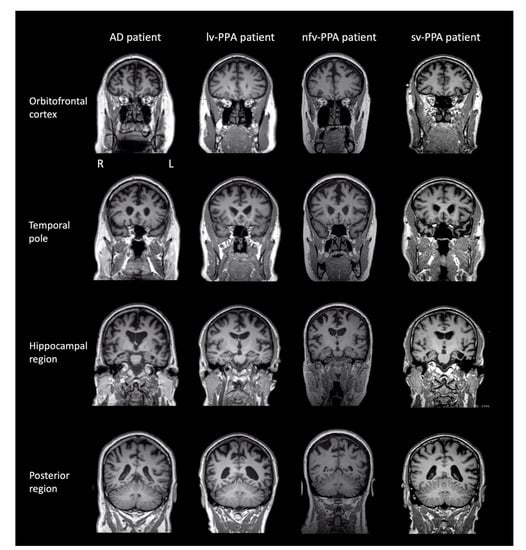

3.1.3. Brain MRI and Clinical Diagnosis

3.2.3. Brain MRI and Clinical Diagnosis

3.3.3. Brain MRI and Clinical Diagnosis

3.4.3. Brain MRI and Clinical Diagnosis